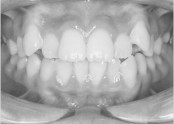

• 치아교정 덧니 교정

• 36